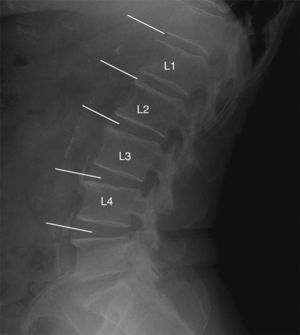

Study technique and evaluation of variablesAccording to the AAC-24 scale, in the lateral lumbar spine X-rays, the aorta anterior and posterior walls were divided into four segments corresponding to the area located in front of vertebrae L1–L4. The segments evaluated were those between an imaginary line parallel to the surface of vertebral bodies and between them. Based on this scale, aortic calcification was scored as 0 (no calcification), 1 (calcification in one third or less of the aortic wall), 2 (calcification in more than one third, but in two thirds or less of the aortic wall) or 3 (calcification of more than two thirds of the aortic wall). It was estimated that there was aortic calcification when images of calcic density were observed in an area anterior and parallel to the lumbar spine, which could appear as diffused white dots, as a linear image of calcification of the anterior and/or posterior aortic wall or as a circumferential image, homogeneous or not, of calcic density. After the sum of both walls, the total score was between 0 and 24 (Fig. 1). At the initial stage of the study, the evaluators received a specific training in the use of the AAC-24 scale and the application of the Kiel et al. radiographic atlas,27 under the supervision of one of the authors (RLA), a radiologist with 18 years of clinical experience. To this end, they all evaluated 10 X-rays with different degrees of aortic calcification, which were later ruled out for analysis.

Lateral lumbar spine simple X-ray with images of calcifications in the abdominal aorta of one participant in the study. The partial scores in the ACC-24 scale (anterior wall+posterior wall) were: Level L1=1 (1+0), level L2=0, level L3=4 (3+1), level L4=2 (0+2) that is an overall score of 7.